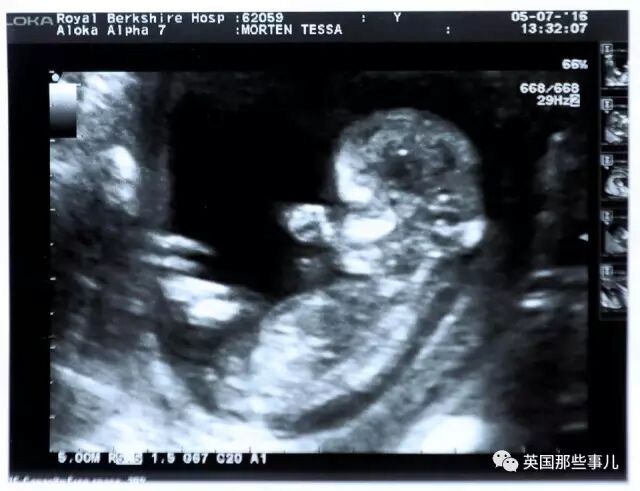

今天故事的主人公, 是一對曾經苦苦“求娃兒”的夫妻… 妻子Tess Morten,今年47歲, 丈夫Neil,今年52歲, 倆口子都來自英國, 他們於2003年,在牙買加舉行了浪漫的婚禮… 由於結婚時倆人都已經人過中年, 因此,從一開始,他們就迫切的渴望給這個家添個小寶寶… 然而,遺憾的是, 在此後長達7年的“求娃兒”之旅中, 他們先是嘗試自然懷孕,但Tess的肚子始終沒有任何“動靜”, 緊接着,他們又跑了許多醫院,看了各種專家門診, 前前後後做了3次試管嬰兒,總計花費超過20000英鎊, 可是,最後卻還是均以失敗告終… 2010年, Tess絕望地發現,自己絕經了…… 儘管,根據英國國家醫療服務體系(NHS)的資料顯示, 英國女性的平均的絕經年齡應該是在51歲, 但,報告中仍然提到,每100位女性中就會有1個在40歲左右絕經… 對於Tess而言,這一切也就意味着, 她不會再排卵了,也就更不可能懷孕了… 那時的Tess和Neil已經徹底放棄了, 他們知道,這輩子,都不可能迎來屬於倆人的愛的結晶了。 為了改善倆人長久以來壓抑、煎熬的心情, 在心理醫生的建議下,他們決定去領養3個孩子, 將自己的愛與關心,傳遞給更多需要幫助的人… 除此以外,夫妻倆還領養了一隻汪星人, 並且,在家裡的後院開闢了一個小花園,沒事就去散散心, 漸漸地,沒有希望就沒有失望, 這對夫妻的生活歸於平靜… 然而, 事實上,儘管夫妻倆在精神上沒那麼大壓力了, 可這些年,Tess一直在忍受着身體上的不適。 因為絕經對於一個女人而言,並不是苦難的結束, 處在這個時期的女性,會出現潮熱、盜汗、睡眠困難、焦慮以及性慾減退等各種不良症狀, 有時候,這些症狀甚至會在正式絕經的前幾個月就開始折磨人… 而Tess則一直經歷着潮熱的不良反應, 於是,在2015年11月,Tess開始接受激素替代療法(hormonereplacementtherapy,HRT),嘗試緩解症狀。 所謂的HRT,是指通過補充激素來治療激素分泌減退或者缺乏所引起的疾病的治療方法。 它對絕經過渡期的月經失調有調節作用,也能夠緩解潮熱及泌尿生殖道萎縮等症狀… (並非所有女性適用,欲嘗試請事先諮詢醫生) 不過,在接受HRT幾個月以後,Tess的感覺反而更不好了, 她的身體開始明顯的臃腫,十分易累,甚至偶爾感到噁心想吐。 就這樣,她不得不去醫院做了更全面的檢查, 而醫生的最初推斷,幾乎讓這對夫妻再次陷入絕望: “在檢查結果還沒出來前,醫生懷疑我可能患上了卵巢癌,他讓我們做好最壞的打算。” Tess說道。 然而,在Tess夫婦忐忑不安地等待診斷結果時, 奇蹟就這樣發生了… 在一次B超檢查中,Tess原本十分忐忑的躺在病床上, 可醫生突然把顯示器轉到了Tess的視線方向,十分激動的指着圖像說: “你的卵巢沒有問題,但我想你需要看看這個。” Tess十分不解的望向屏幕, 就這樣,她在B超圖中看到了一個嬰兒,她幾乎脫口而出: “啊,這是我的嗎?” 這?已經絕經近7年還能懷孕??!! 那一刻的Tess徹底震驚了, 原本,她緊緊握着一旁護士的手,擔心着最壞的消息, 可她萬萬沒想到,自己竟然是懷孕了??!! “我哭了,我從來沒想過這事兒會發生,我已經絕經了,我明明不可能懷孕的。” 現在回憶起來,Tess依然難掩激動… 回到家後,Tess立馬把這個喜訊告訴了Neil: “那天Neil要上班所以沒和我一起去醫院,他很擔心,因為我一直沒有回電話, 當我看到他的時候,我低聲說,不是癌症,是我肚子裡有小寶寶了。“ 顯然,Neil也覺得非常不可思議,倆人一邊開心不已, 另一邊,又非常擔心搞出什麼烏龍, 第二天,他們又去重新檢查了一次: “結果仍然是好的,那時我已經懷孕三個月了,是個可愛的小女孩, 後來,因為我們年紀都比較大了,我們又做了很多測試,好在,一切都正常健康…” 2017年1月,等待了14年後,這對夫妻終於迎來自己的女兒,Molly, 小姑娘出生體重近7斤,非常的健康… 如今,小Molly已經8個月大了, 這個有愛的家庭已經出去旅行了好幾次… “當我們知道這是一個女孩的時候,Tess就說要給她起名Molly,代表着奇蹟的意思。“Neil說道… 時至今日,每當看到Molly的臉,Tess依然感到不可置信… 那麼,究竟是什麼原因帶來了這次奇蹟呢? 按照常識,對於女性而言,懷孕的大前提即是有正常排卵, 可是,已經絕經近7年的Tess,照理說應該早就不排卵了呀? 專家認為,這一切可能與她此前接受的HRT有關。 英國生育協會主席Adam Balen表示, 一個絕經7年的女性,再次懷孕的可能是微乎其微的, 但是,也有一些案例也顯示, 一些女性即使絕經後,她們的卵巢中仍可能會剩留一些卵泡: “HRT藥物中的激素可能會導致這些剩餘被激活釋放,無意中啟動了排卵過程…”Adam Balen說道。 比如說,1997年,英國就曾經有一位59歲的婦女, 因絕經接受了HRT之後發現自己懷孕,並隨後生下了一個十分健康的兒子, 但針對Tess的案例,Adam仍然感嘆道: “不過,絕經7年還能懷孕,我真的聞所未聞,真的太神奇了。” 除此以外,生殖醫學主任Geeta Nargund後來也在媒體的採訪中表示, Tess的情況絕對是個奇蹟…. “在HRT中,確實可能會出現女性自發排卵的病例,但這個幾率並不高, 尤其是,即便是出現了排卵,也大多發生在絕經期前後不久, 像Tess這樣已經完全絕經卻排卵受孕的,實屬罕見…” 好吧…. 無論如何,祝福這對夫妻, 這個小生命,確實人如其名,是個奇蹟啊…… |